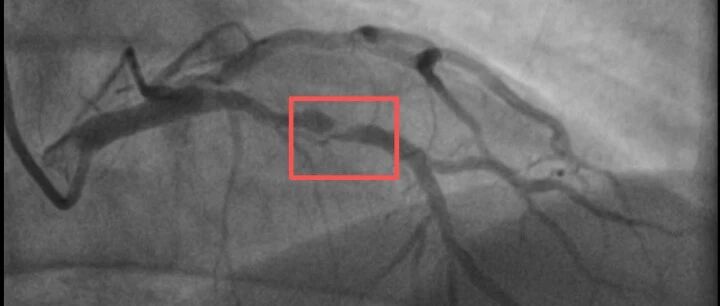

急性心肌梗死是最危险的急性胸痛疾病之一,被称为心血管疾病中的“头号杀手”。谈及心肌梗死的先期症状,成都市急救指挥中心专家、培训科科长胡承志表示,心肌梗死的症状比较多,常见的比如胸痛、胸闷,感觉到有点喘不上来气,但也有些人表现为肩膀痛、手痛、手抬不起来,甚至有些人表现为背痛、牙齿痛,有这些症状以后,都要警惕小心。